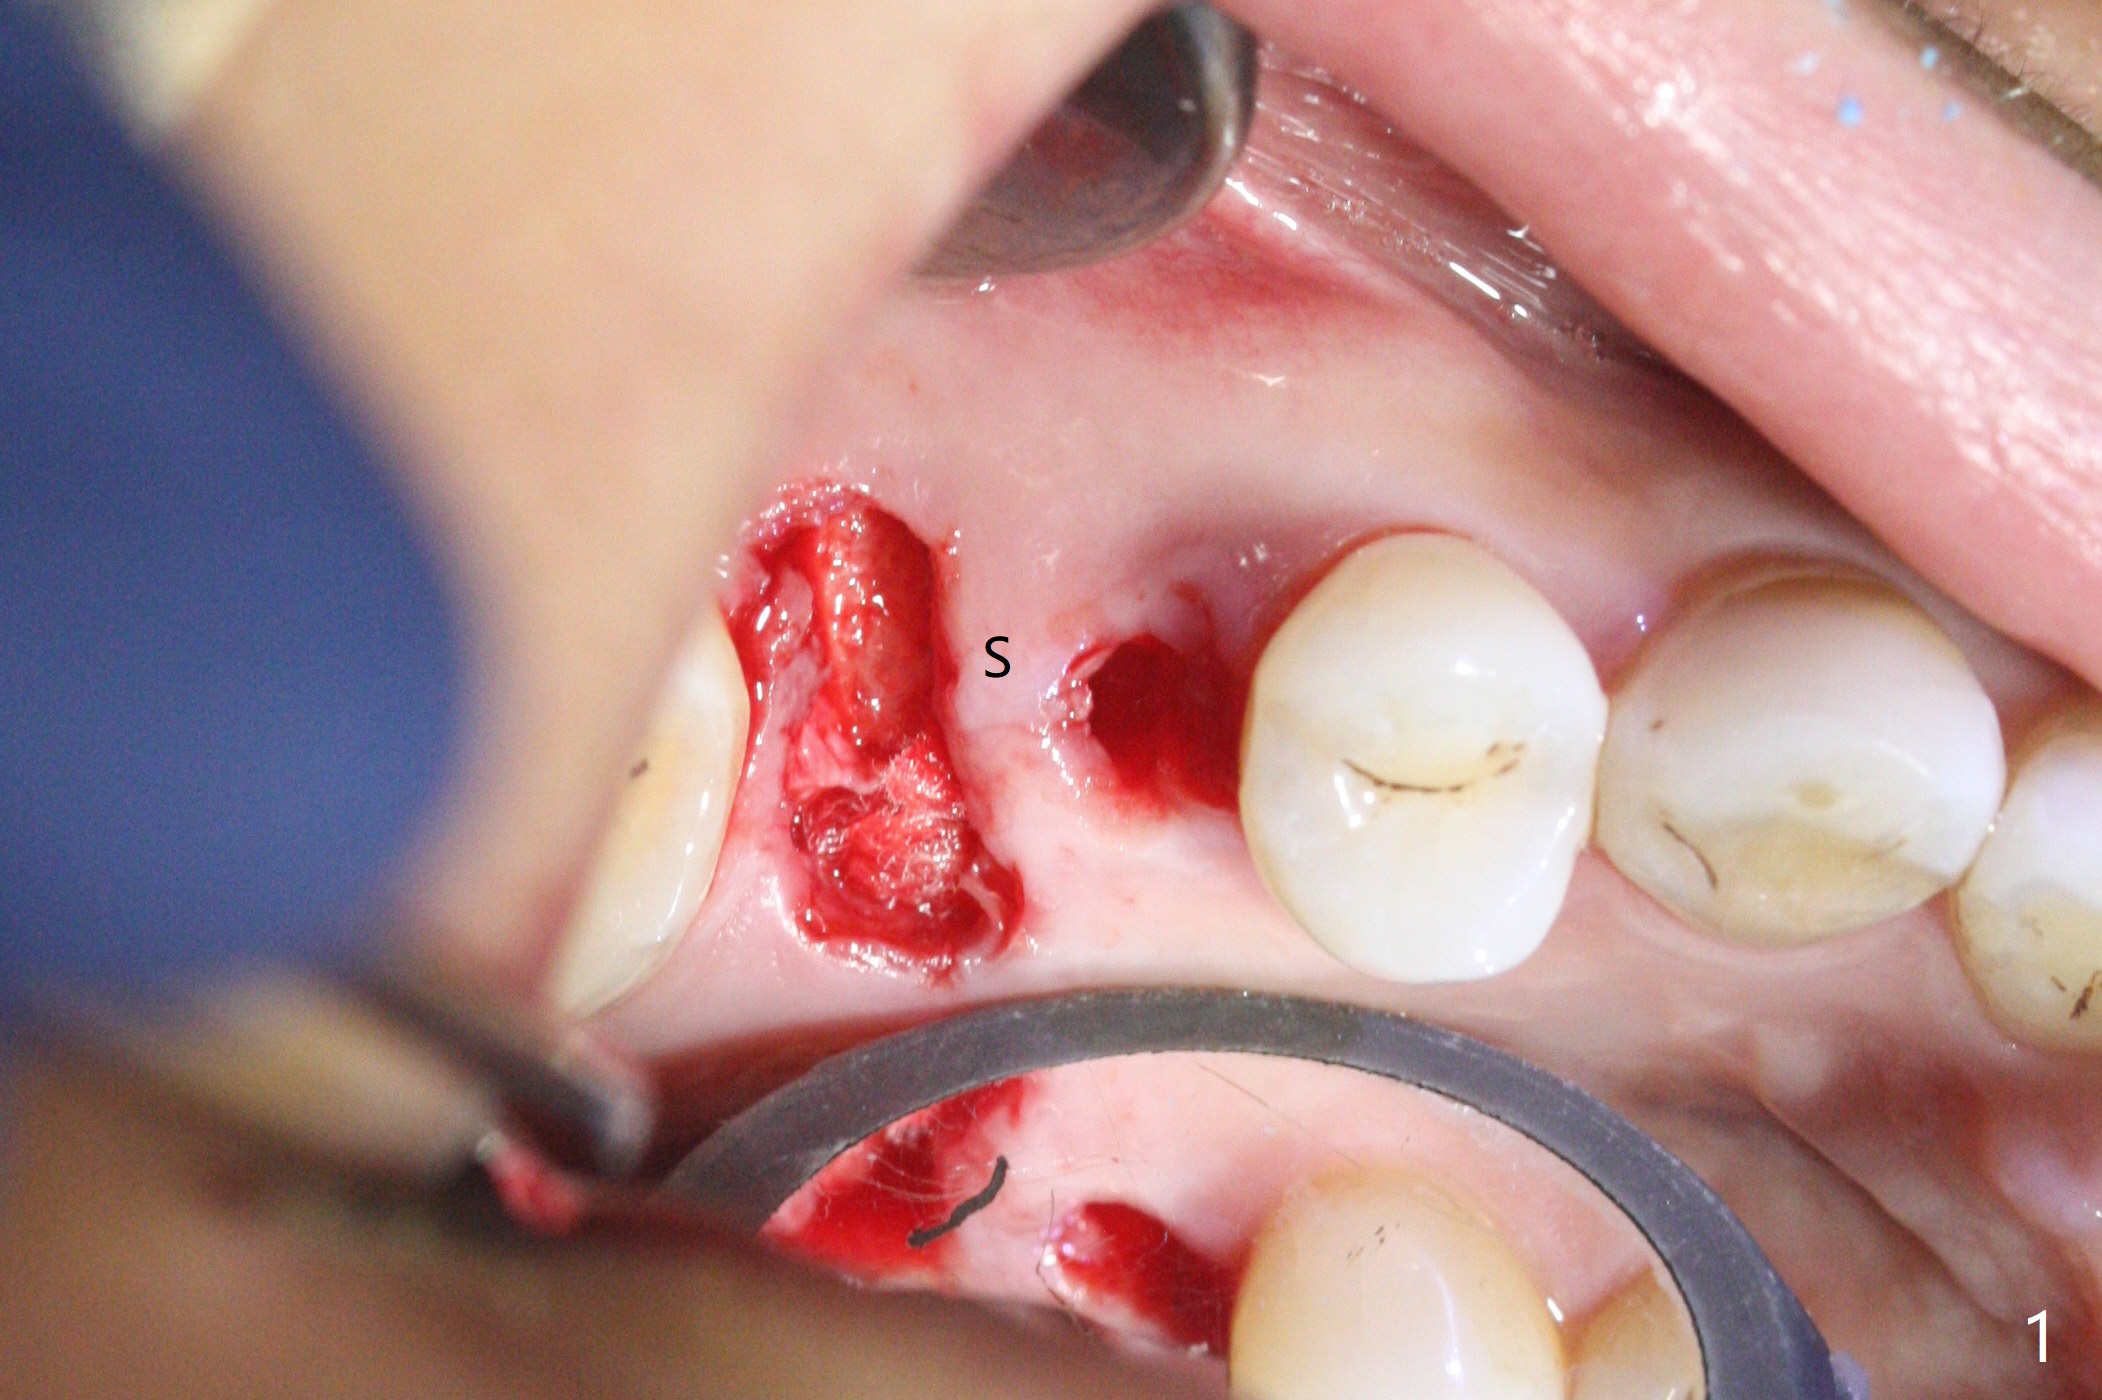

When the residual roots of the tooth #3 are removed, there is a gingival band over the septum (Fig.1 S). Osteotomy (Fig.2 yellow circle) would tear it off. To save the soft tissue, the buccal attachment is severed (Fig.3 black line), the flap is rotated palatal (Fig.3 curved arrow) and sutured in place (Fig.5 S). After sinus floor breakdown (use of sinus drill for 16 mm) and use of membrane lifter/water, two pieces of PRF membrane are inserted. The membrane is so slippery that it is easy to enter the sinus for further sinus membrane lift and later allograft placement (Fig.4 *). A 4.5x10 mm dummy implant is placed with high torque after 4x7.3 mm drill with 3 mm stopper so that 4.5x7.3 mm drill with 1 mm stopper is used before placement of a 5x8.5 mm final implant with ~ 35 Ncm (Fig.5-7). The patient reports anterior sinus wall tenderness with right nasal discharge a few days postop. The provisional has mobility without tenderness 1 week postop. It appears that the sinus membrane has been involved, which is quickly repaired probably by PRF. There is no pain when a 5.2x4(2) mm cemented abutment is torqued at 30-35 Ncm before impression (Fig.8). The surrounding soft tissue is healthy. When the permanent crown is delivered, the patient feels light pain when she bites hard. The discomfort persists 4 months post cementation (Fig.9). The crown/abutment is replaced with a healing abutment (Fig.10). There is no bone loss 4 months post healing abutment placement (14 months post implant placement, Fig.11). Upper Molar Immediate Implant, Prevent Molar Periimplantitis (Protocols, Table), Trajectory II, 31 Flap Not Transferred Xin Wei, DDS, PhD, MS 1st edition 07/26/2019, last revision 10/05/2020